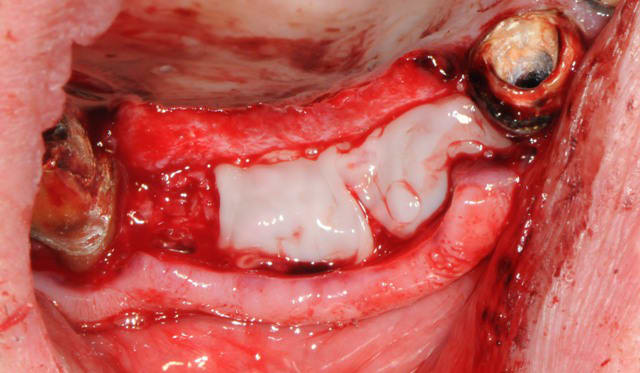

pour éviter la fissure, nous aurions pu faire une décharge vestibulaire à la lame 15, mais il me semblait important de "tendre" toutes la demie arcade, pour favoriser la tenue des implants en particulier la 5 qui subie en même temps un soulevé de membrane.

La fissure c'est un des petits soucis sans trop de conséquences si membrane par dessus

De plus si une membrane est placé, plus besoins de combler la tranchée non ?

la membrane n'est pas forcement obligatoire, ça dépends de tes habitudes et de la façon de faire, j'utilise beaucoup le VitalOs, mais quelques fois une simple éponge en protection, pour le cas du Dr SP... il a mis des copeaux et du prf, c'est bien aussi.